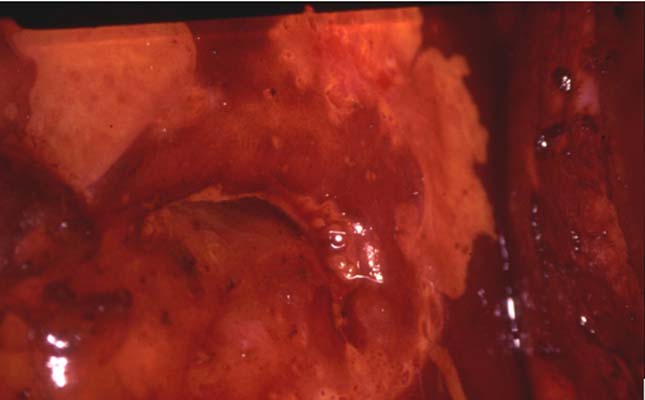

Régularisation d’une TAGI